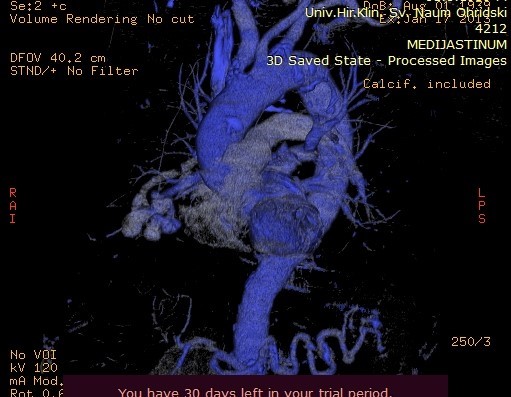

Image 4. MDCT of the lungs, contrast series in the coronal plane, showing a cluster of blood vessels.

Image 5. Maximum Intensity Projection (MIP) reconstruction of the AV fistula at the level of arterial and venous blood vessels in the right lung.

Image 6. Maximum Intensity Projection (MIP) reconstruction showing AV shunting into the pulmonary arteries.